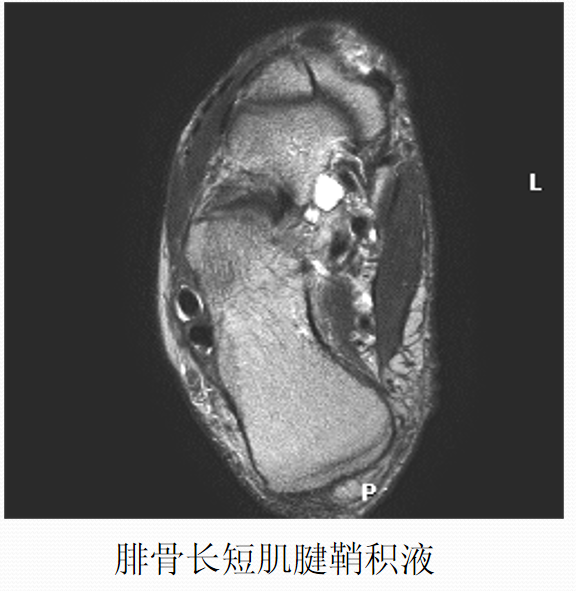

外侧:腓骨长肌腱、腓骨短肌腱

胫前、胫后肌腱撕裂

病因病理机制:

• 好发于中年人,胫骨前肌腱多见于登山运动员。

• 类风湿性关节炎、有副舟骨患者好发。

• 足踝运动障碍、疼痛。

• 胫骨后肌腱是维持足弓的重要力量,撕裂后易出现扁足。

MR表现:

• 胫骨前肌腱较少发生撕裂,一旦发生,多为全肌腱损伤

• 胫骨后肌腱出现横截撕裂或纵行撕裂

• 肌腱增粗,原本椭圆形的肌腱横断面变成圆形

• 可为横向或纵向撕裂;完全或部分撕裂

• 相应的腱鞘积液和鞘膜增厚

• 邻近关节见骨关节炎表现